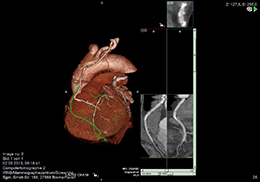

Bei der Cardio-CT handelt es sich um eine nicht-invasive Schnittbilduntersuchung zur Darstellung der Herzkranzgefässe (Koronarien). Mit modernen Multislice-CT-Scannern ist es heute möglich, auch die kleineren herzversorgenden Koronarien adäquat darzustellen und mögliche Verengungen zu erfassen.

Die Cardio-CT dient zur Untersuchung von Patienten mit geringen oder atypischen Herzbeschwerden zur Diagnose einer koronaren Herzerkrankung (KHK) und zur Beurteilung von Gefäßverkalkungen (Agatston-Calciumscore). Für schwerkranke Patienten mit hochgradigem Verdacht auf Verengung der Koronarien oder sogar Herzinfarkt ist weiterhin die rasche Untersuchung mittels eines Herzkatheters angezeigt. Da die Cardio-CT im wesentlichen wie eine normale Thorax-CT abläuft, sind die notwendigen Laborbestimmungen dieselben. Wie für diese ist auch die Injektion eines jodhaltigen Kontrastmittels erforderlich (siehe auch den Abschnitt Computertomographie).

Die Cardio-CT dauert 20-30 Minuten und wird in Rückenlage durchgeführt. Zunächst werden Ihnen EKG-Elektroden angelegt, damit die CT-Aufnahmen mit dem Herzschlag synchronisiert werden können. Wenn die Herzfrequenz des Patienten erhöht ist, kann die intravenöse Verabreichung von β-Blockern erforderlich sein.

Zur Ermittelung des Verkalkungsgrades der Koronarien (Agatston-Calciumscore) erfolgt zunächst ein Scan ohne Kontrastmittel. Für die Darstellung der Koronarien werden danach 80-120ml Kontrastmittel rasch über einen venösen Zugang injiziert und vom Brustkorb im Atemstillstand über mehrere Sekunden weitere Scans durchgeführt. Das dabei auftretende Wärmegefühl ist völlig normal. Die Befundung der erstellten Aufnahmen erfolgt an Hochleistungsrechnern durch unsere Radiologen mit Hilfe spezieller Programme nicht nur im Hinblick auf die Koronarien, sondern für den gesamten Brustraum.